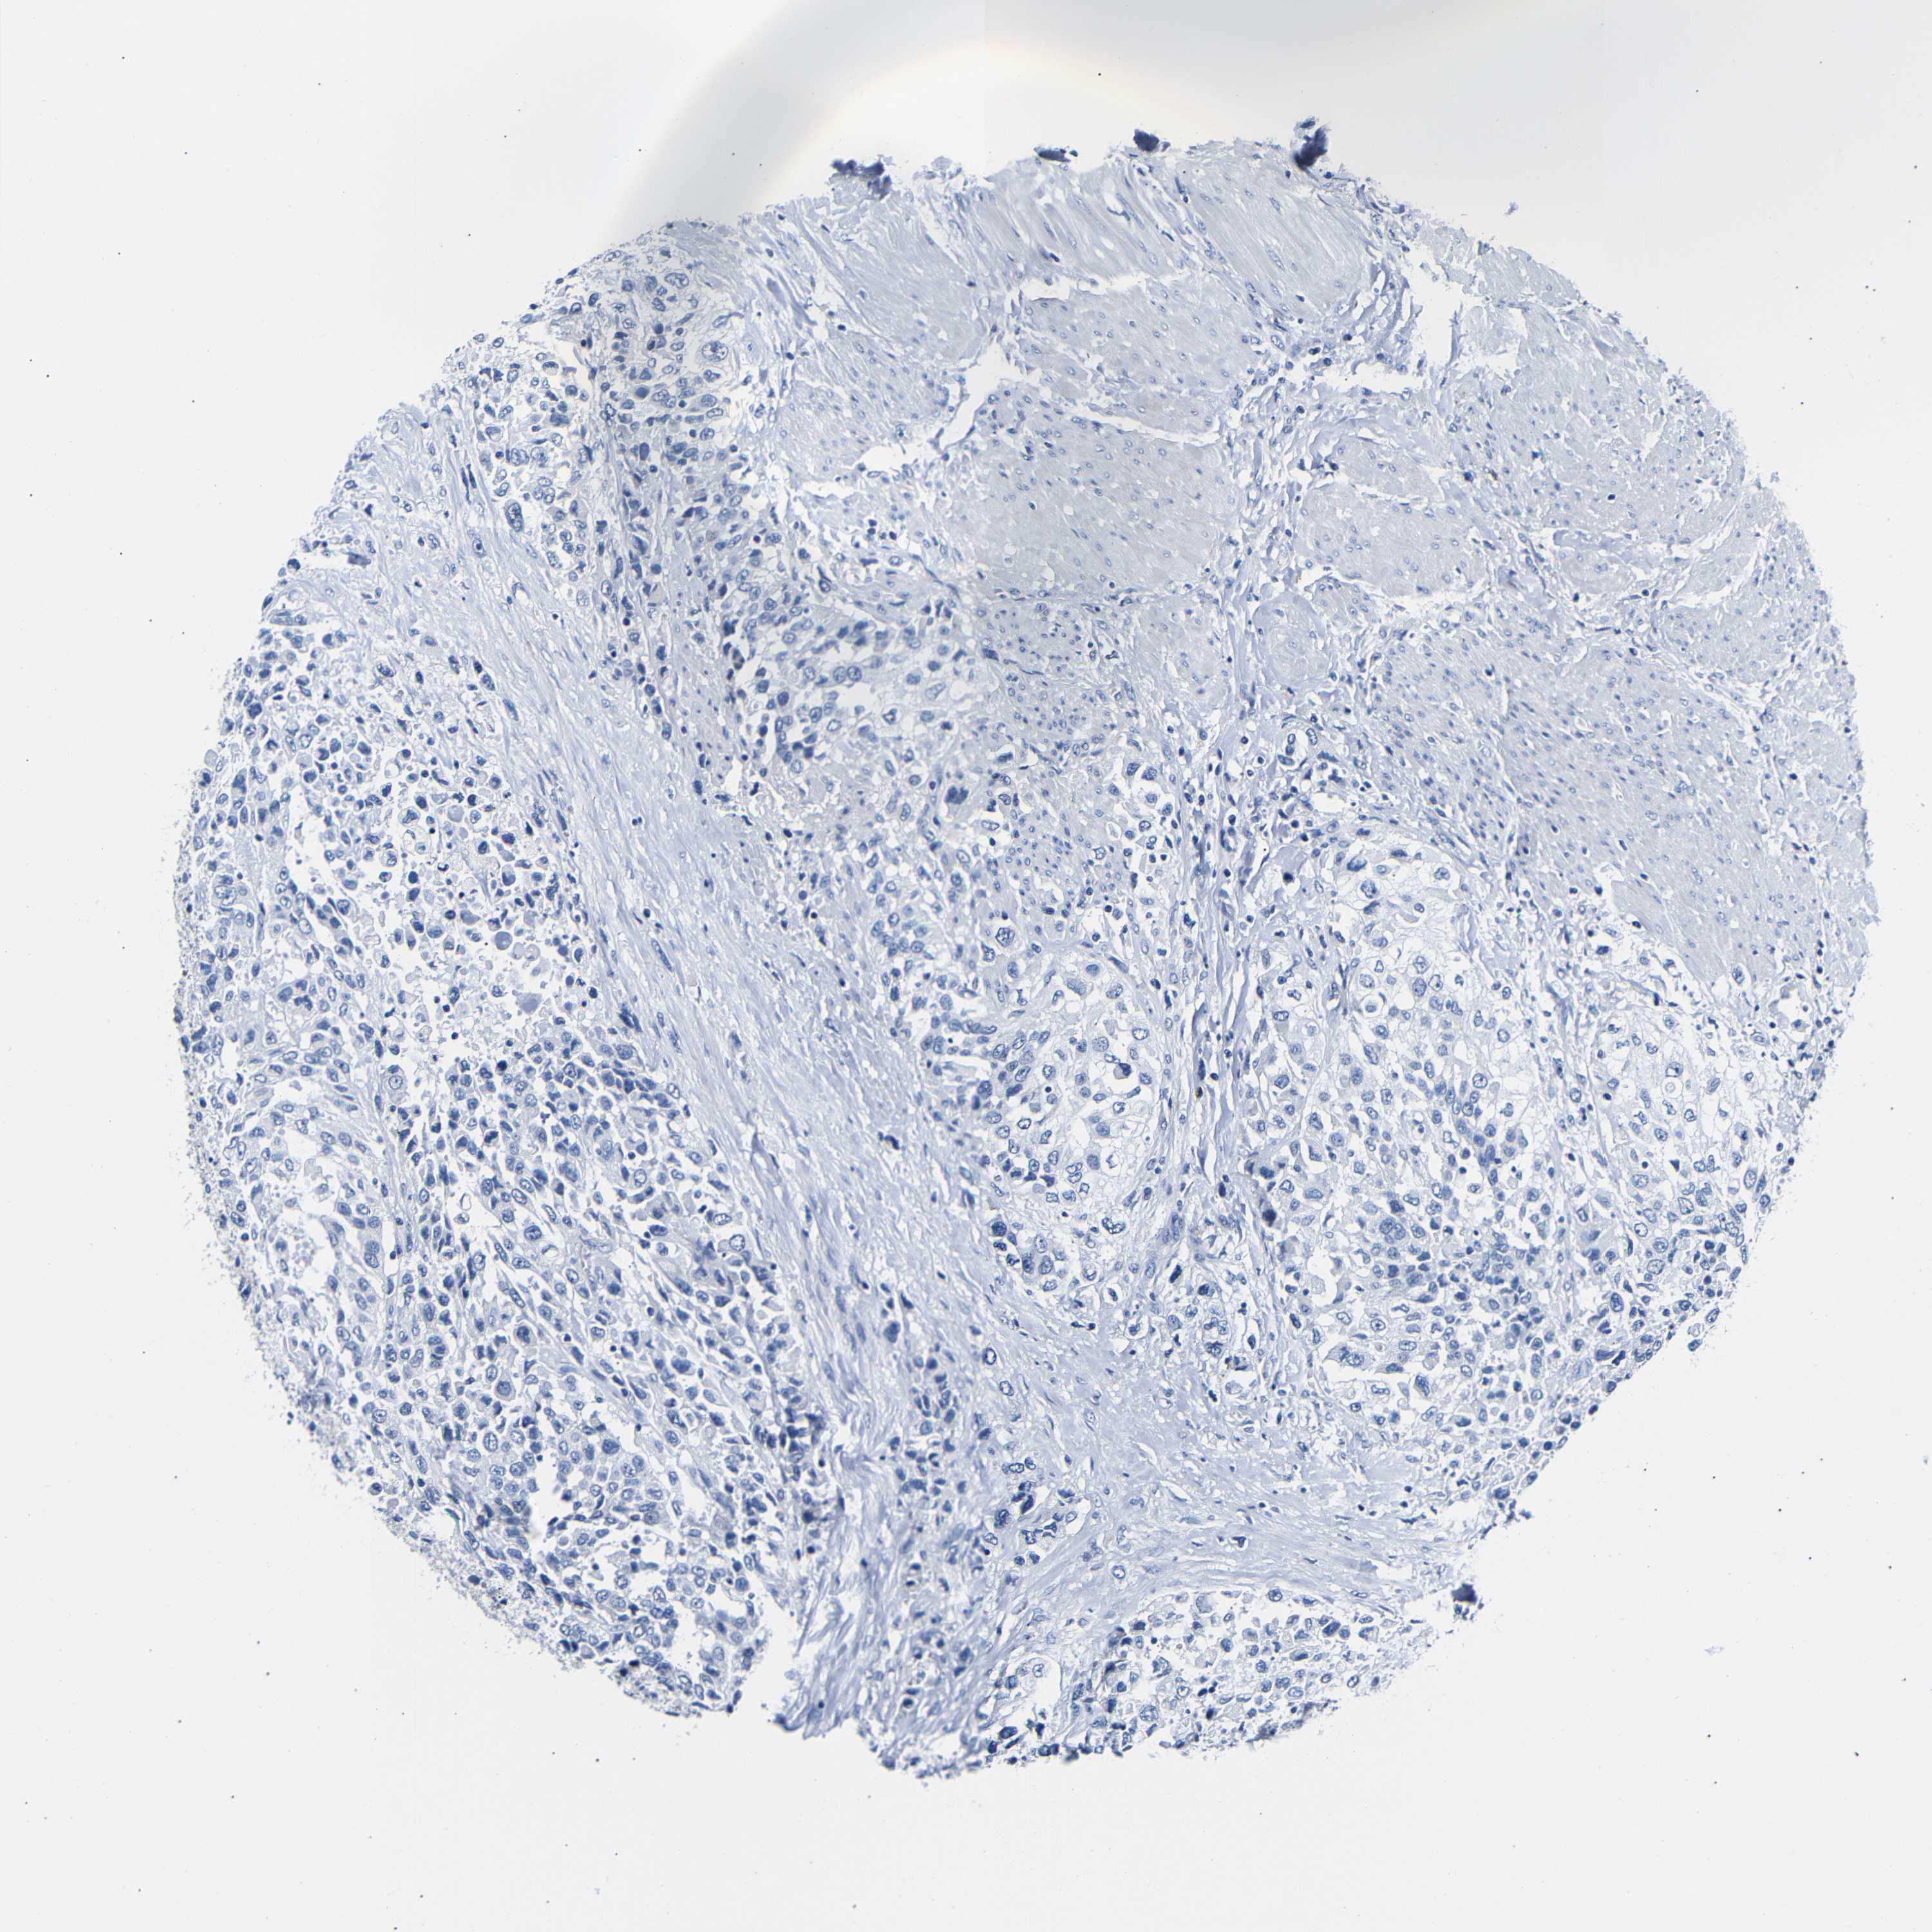

UROTHELIAL CANCER - Protein expressioni

A mouse-over function shows sample information and annotation data. Click on an image to view it in a full screen mode. Samples can be filtered based on level of antibody staining by selecting one or several of the following categories: high, medium, low and not detected. The assay and annotation is described here.

Note that samples used for immunohistochemistry by the Human Protein Atlas do not correspond to samples in the TCGA dataset.

Antibody stainingi

Antibody staining in the annotated cell types in the current human tissue is reported as not detected, low, medium, or high, based on conventional immunohistochemistry profiling in selected tissues. This score is based on the combination of the staining intensity and fraction of stained cells.

Each image is clickable and will lead to virtual microscopy that enables deeper exploration of all samples and also displays staining intensity scores, fraction scores and subcellular localization as well as patient and tissue information for each sample.

Antibody HPA013392

Antibody HPA015600

Antibody CAB004417

Staining

High

Medium

Low

Not detected

Intensity

Strong

Moderate

Weak

Negative

Quantity

>75%

75%-25%

<25%

None

Location

Nuclear

Cytoplasmic/membranous

Cytoplasmic/membranous,nuclear

Urothelial carcinoma, Low grade

Urothelial carcinoma, High grade